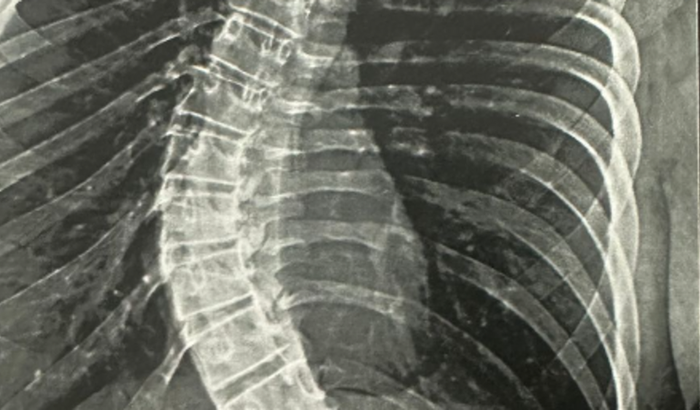

Meu nome é Julio Henrique e preciso arrecadar R$75.000,00 para a cirurgia de Escoliose da minha irmã Ana Karoliny. Onde não tem outras opções de tratamento. Ela tem apenas 16 anos e a cirurgia neste momento será o ideal para que o quadro não se agrave e futuramente não tenha maiores consequências.